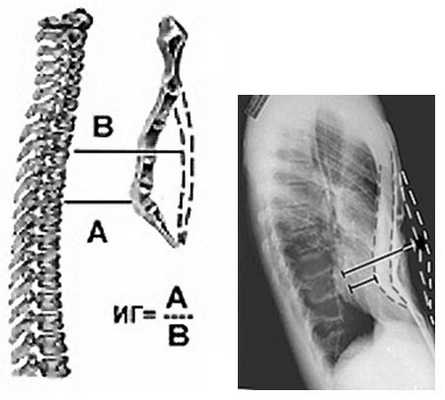

Для определения степени деформации применяется индекс Гижицкой - это частное от деления наименьшего расстояния между задней поверхностью грудины и передней поверхностью тел позвонков на наибольшее. Эти расстояния измеряются по боковым проекциям рентгенограмм грудной клетки.

СтепеньИндекс Гижицкой1от 0,9 до 0,72от 0,7 до 0,53от 0,5 до 04от 0 до -0,5